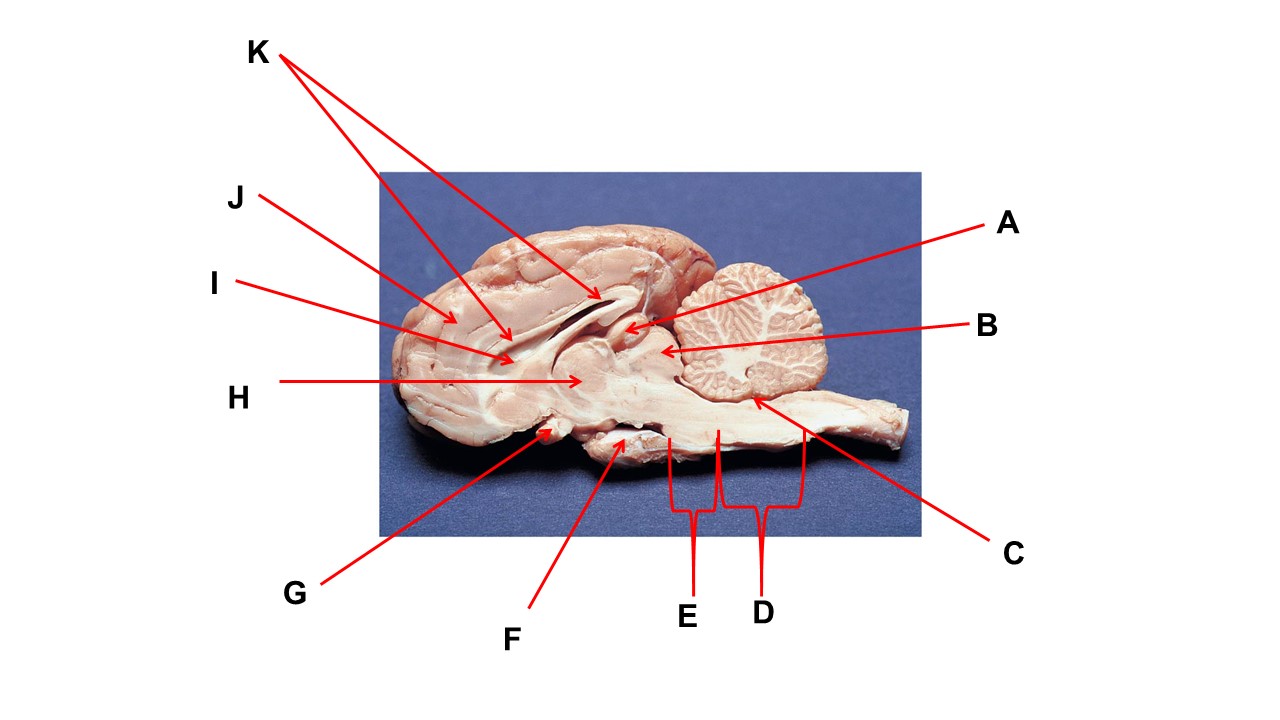

Name the structure at the tip of arrow K.

ventral root

Name the structure at the tip of arrow A.

pineal gland

The cavity at the tip of arrow I is the _____.

lateral ventricular

The cavity at the tip of arrow I is filled with ______.

cerebrospinal fluid

Name the structure at the tip of arrow F

mammillary body

Name the structure at the tip of arrow A.

pineal gland

Name the structure at the tip of arrow G

optic chiasma

Name the nerve at the tip of arrow H.

optic